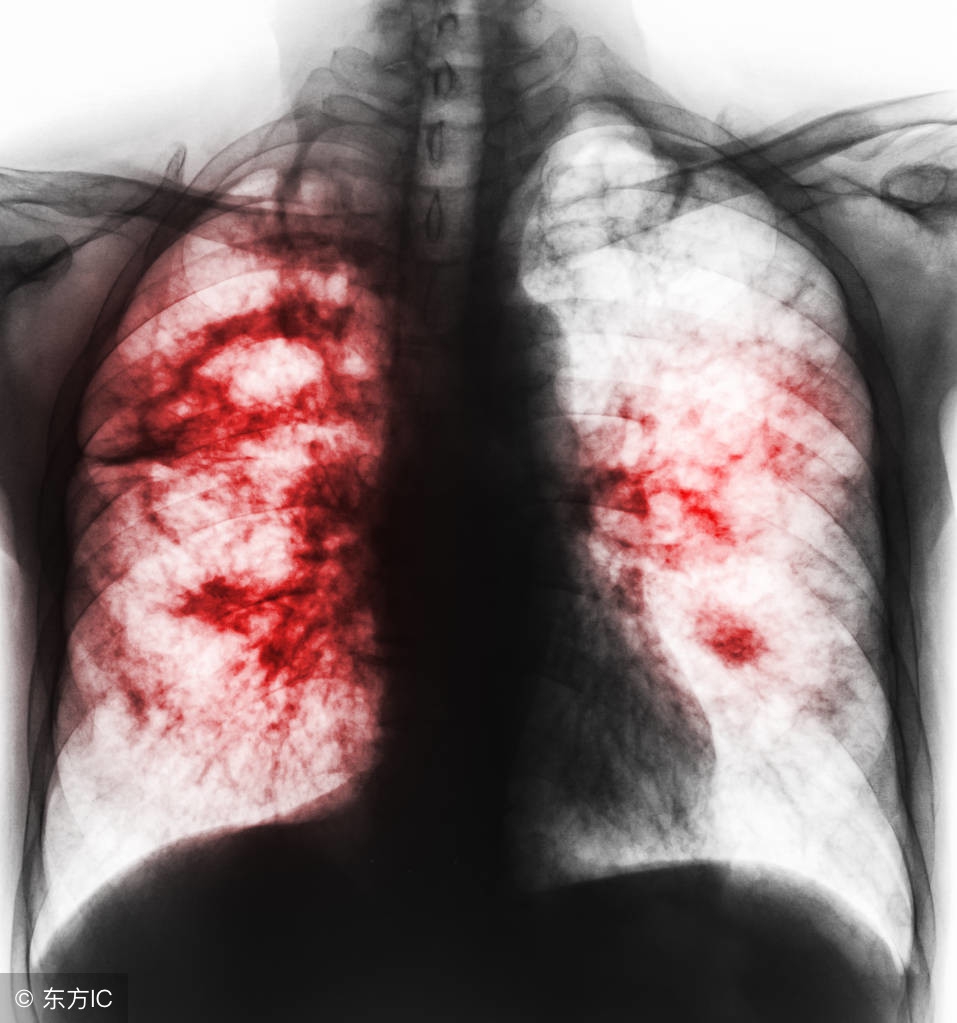

很多肺癌患者,由于没有早期发现病症,耽误了最佳治疗时间,发展成为肺癌中晚期,尽管治疗效果没有早期好,但肺癌中晚期治疗方案也会根据患者自身的情况进行改进,中医对于中晚期肺癌治疗有一定的研究。肺癌中晚期治疗方案主要是抑制病情再度恶化,减缓患者病痛折磨,提升患者的生活品质为主要原则,这一点上,中医食疗偏方很有发言权。

当肺癌发展到中晚期,病症表现较为明显,首先,患者应该注意止痛和心理治疗,疼痛是晚期肺癌患者最难以忍受的痛苦,通过药物进行医治,同时,家人应该多关心患者,照顾患者的情绪,让患者保持乐观积极的治疗心态。